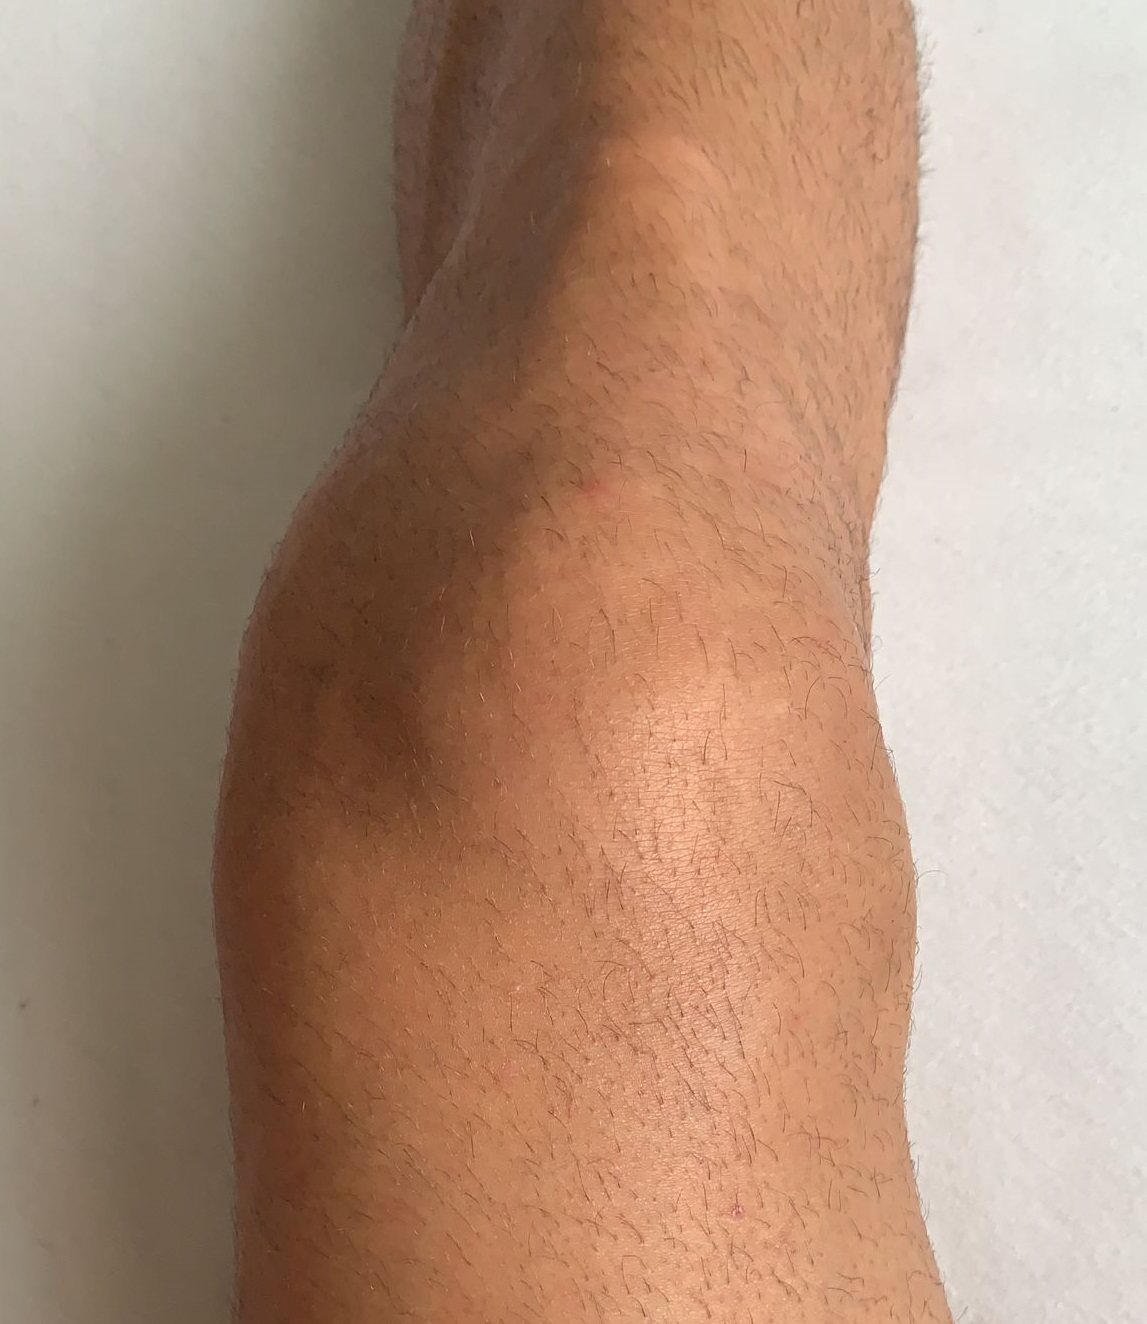

Kneeswell

If the knee starts to inflame, first sign will be swelling up. Swelling up of the knee is a way for body to try to defend it self from the damage by overlubricating the joint and it is a sign that something is not right. Inflamed joint produces cytokines that further promote degrading of the cartilage that induces more inflammation and the vicious circle is started.